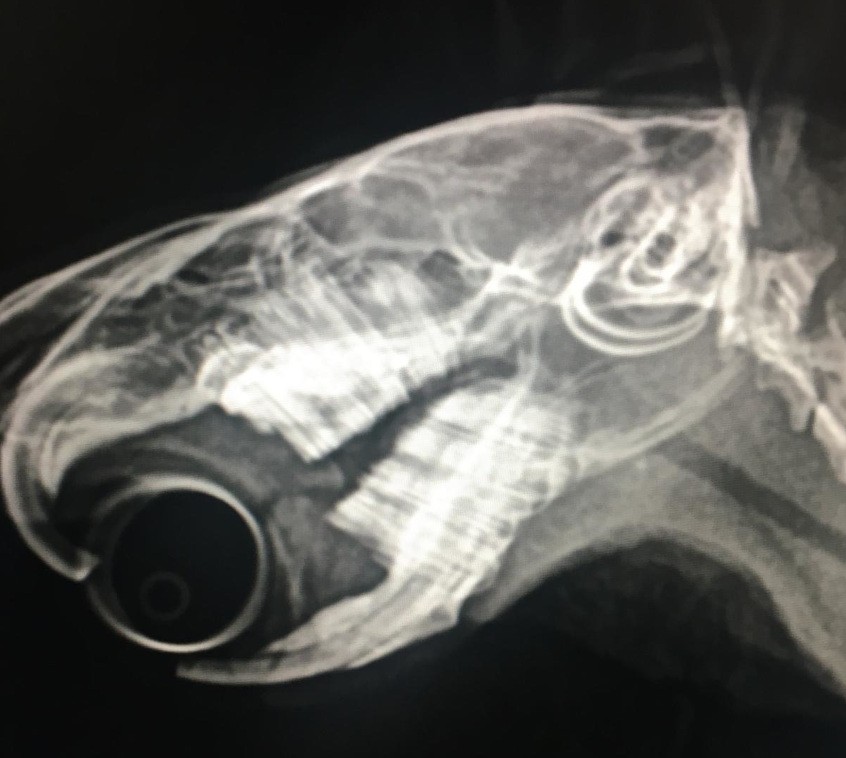

Fogreszelés

Fotó: dr. Pálosi Csaba

– Megelőzésként mindenekelőtt fontos az időszakos állatorvosi száj- és fogvizsgálat a rendszeres súlyméréssel együtt. A tengerimalac, a nyúl, csincsilla teljes fogazata gyökértelen, a metszőfogak mellett az előzápfogak és zápfogak gyökércsatornája is nyitva marad, a fogak mindegyike állandóan nő. Ezért számukra különösen fontos az egész napos rágcsálás, mivel a fogak közti állandó súrlódás biztosítja azok megfelelő kopását. A fogak túlnövése gyakran a nem megfelelő és rostszegény étrend eredménye, de kiválthatja helyi fertőzés, kicsi korban bekövetkezett sérülés, esés, állkapocs- vagy egyéb sérülés, a rács erőteljes rágása is a kiváltó okok közé sorolható, de genetikai okokra is visszavezethető. Ha örökölt betegségként jelentkezik (pl. a kétévesnél fiatalabb egyedeknél), élete végéig időszakonkénti csiszolást igényel. Ha fennáll a fogtúlnövés gyanúja, a pontos diagnózis megállapítására az alapos kivizsgálás mellett röntgenvizsgálat is szükséges. Megelőzésképpen biztosítani kell az állat számára, hogy jó minőségű füvet és szénát rágcsálhasson egész nap. Ezenkívül el kell látni rágcsálóknak szánt különféle anyagokkal, például vegyszermentes, nem mérgező gallyakkal a gyümölcsfáról lemetszve, vagy rágófával. Ez nemcsak a fogaknak jó, hanem némi szórakozást is nyújt a kisállat számára. A tengerimalac és a nyúl naponta egy teáskanálnyi késztápnál nem kellene többet kapjon. A tengerimalacnak gyakran adnak száraz kenyeret, hogy azt rágja, pedig az nem megoldás a fogak koptatására, mert a kenyér a szájba kerülve azonnal megpuhul, de egyébként sem javasolt könnyen emészthető szénhidráttal táplálni a tengerimalacot. Téves az a felfogás is, miszerint a tengerimalacnak nincs szüksége ivóvízre. Nehéz lehetne megítélni, hogy mennyi zöldségféléből, gyümölcsből származó nedvtartalom fedezné a napi folyadékszükségletét, éppen ezért mindig kell legyen a tengerimalac előtt víz, ami a legpraktikusabb, ha önitatóból jön – hangsúlyozta a szakember.

Túlnőtt fogak

Reszelés után